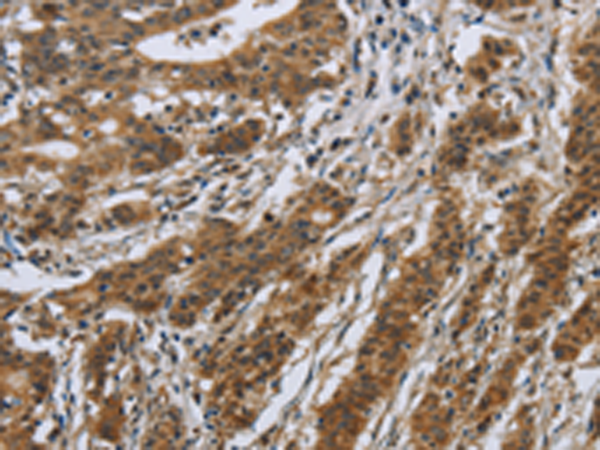

分类: 科研抗体货号: P11850别名: IL-31应用: WB,IHC反应种属: Human